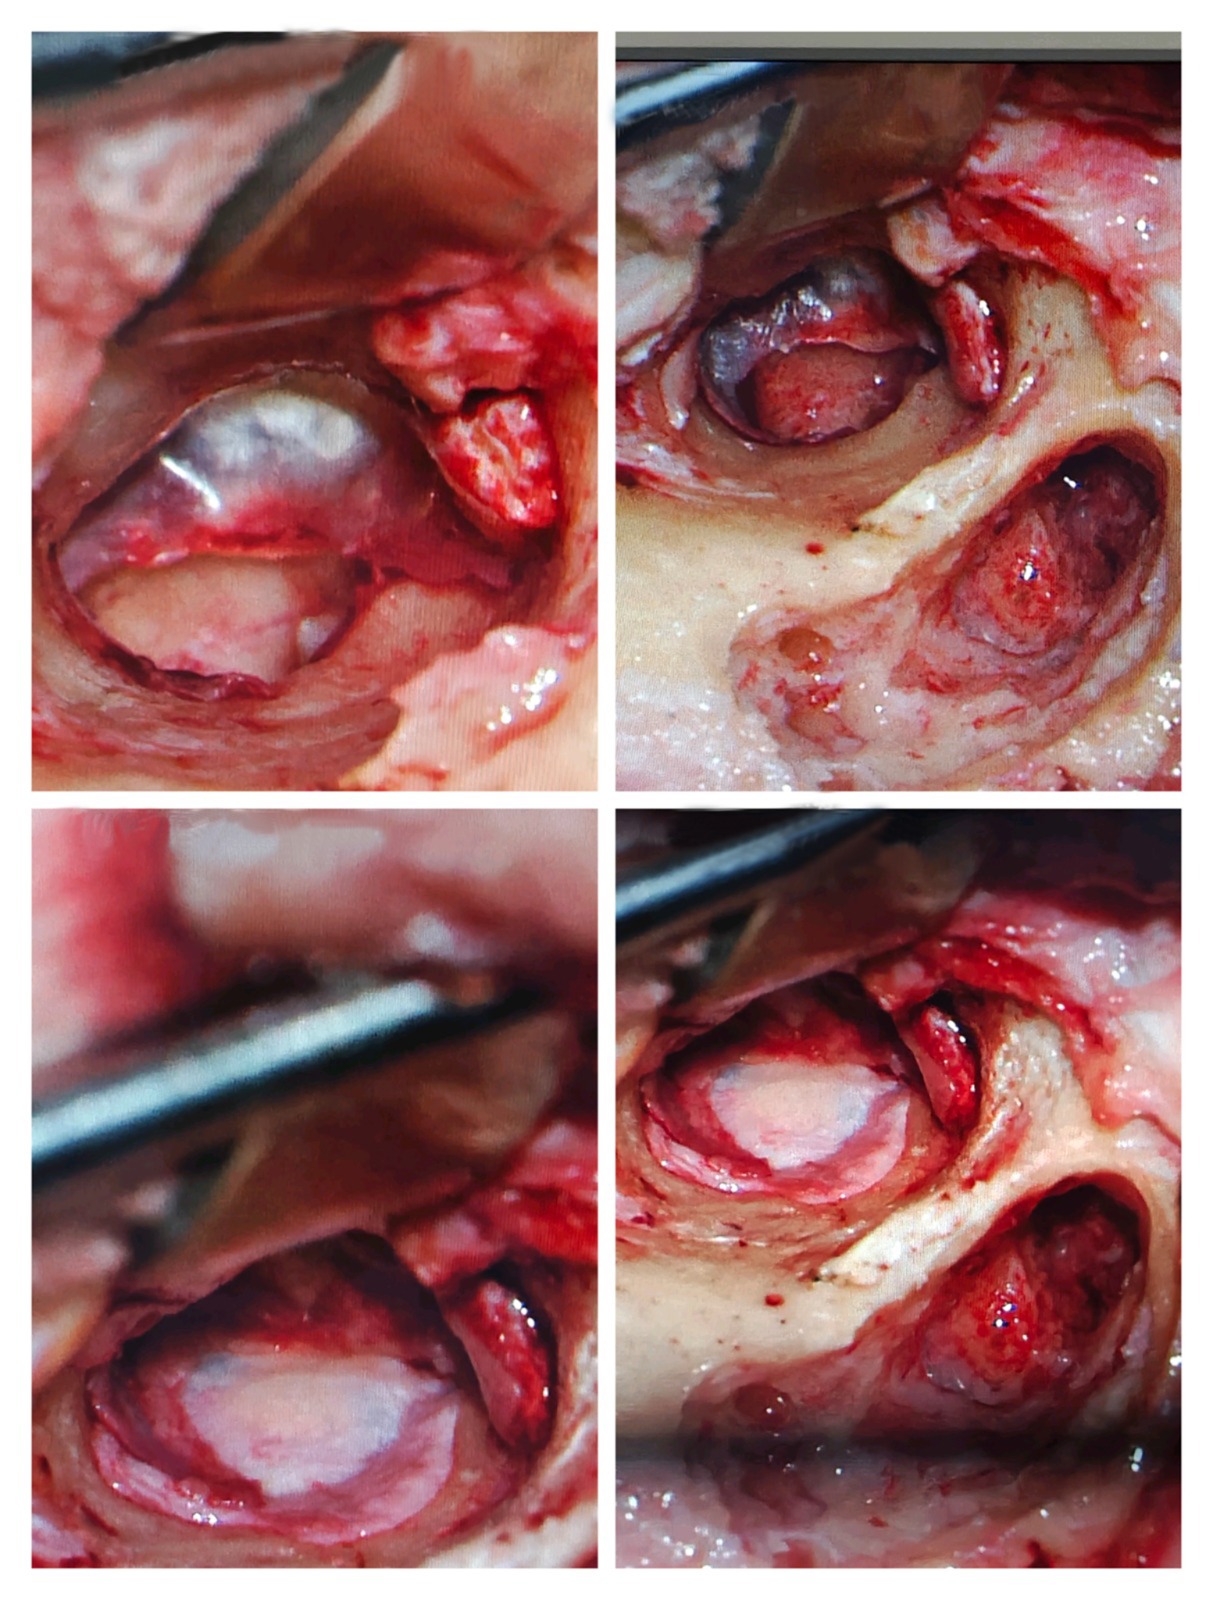

2. Stapedotomy (Otosclerosis Hearing Surgery)

Stapedotomy is performed when the stapes bone becomes fixed due to otosclerosis, causing hearing loss.

Dr. Muddazir replaces the fixed stapes bone with a prosthetic, restoring natural sound conduction.

3. Ossiculoplasty (Middle Ear Bone Reconstruction)

Ossiculoplasty reconstructs or replaces damaged ossicles (hearing bones: malleus, incus, stapes).

4. During the Procedure

- Clear access without large incisions

- Precise handling of microscopic structures

- Minimally invasive techniques

- High-definition microscopes

- Infection control standards

- Nerve-monitoring systems

- Gentle tissue handling